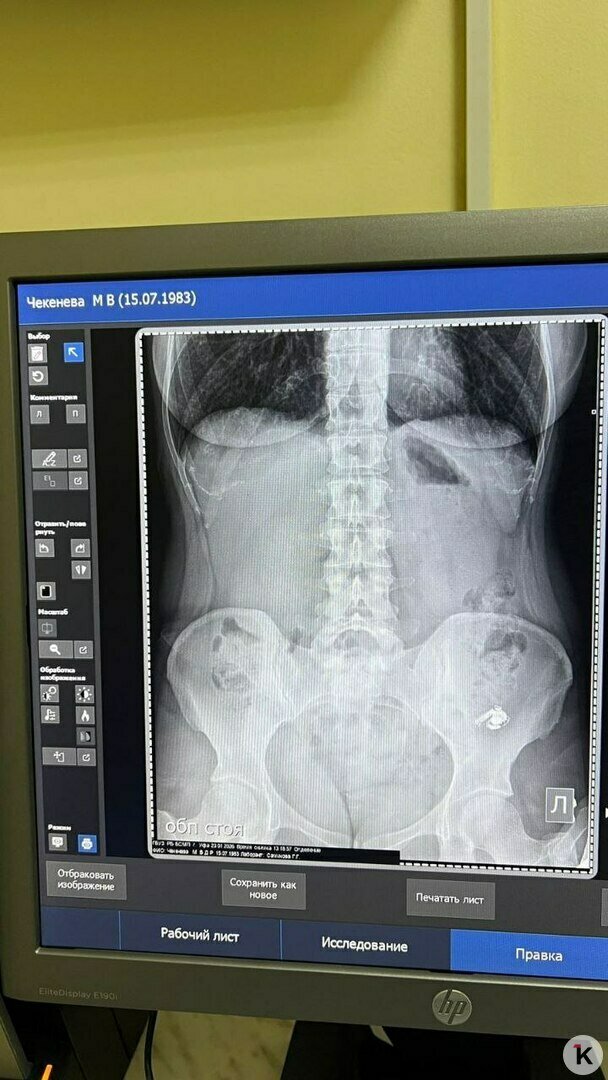

Повторный снимок, к счастью, подтвердил, что всё идёт как надо, инородный предмет постепенно опускается ниже по ЖКТ. Ей рекомендовали мягкую диету для улучшения перистальтики кишечника и отправили ждать дальше. Наконец, поздно вечером на вторые сутки проблема благополучно разрешилась.